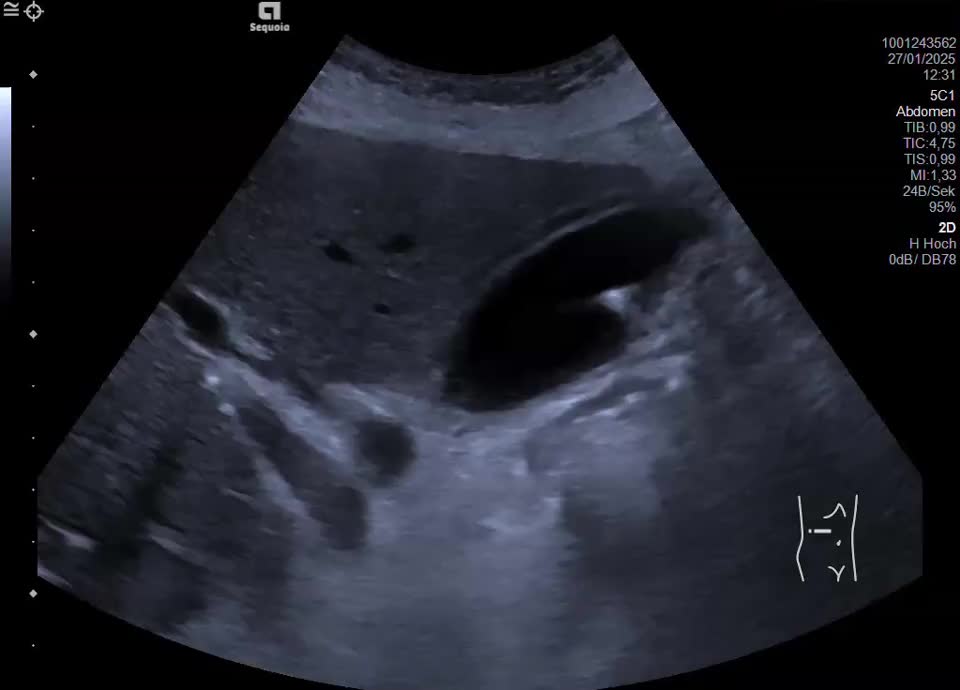

Acute cholecystitis

Fixiertes Konkrement im Ductus cysticus mit konsekutivem Gallenblasenhydrops und Cholezystitis (nebenbefundlich Sludge und Cholezystolithiasis)